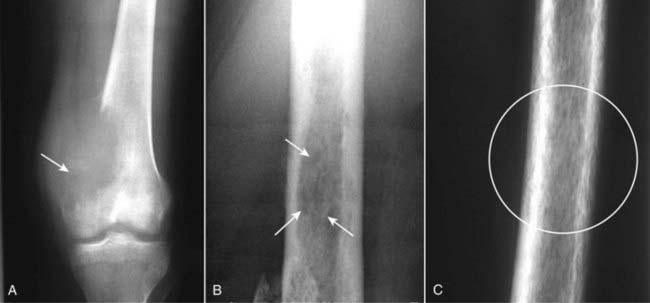

Figure 21-20 Three patterns of lytic bone lesions.

A, A solitary bone lesion with a gradual zone of transition between it and the normal bone and complete destruction of the cortex (solid white arrow) is called a geographic lesion. B, Several ill-defined lytic lesions (solid white arrows) with indistinct margins imply a more aggressive malignancy. This is called a moth-eaten pattern. C, A close-up of the femur shows innumerable, small, irregular holes in the bone (white circle) called a permeative pattern. Permeative lesions are called round cell lesions for the shape of the cells that produce them. Such lesions include Ewing sarcoma, neuroblastoma, myeloma, and leukemia.